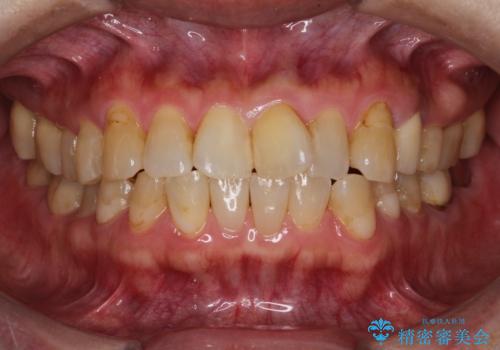

- 前歯のガタガタを主訴に来院されました。

上の歯の前突も気になってたため、奥歯の遠心移動も行いながらインビザラインにて治療を行いました。

前歯も下がり満足していただきました。